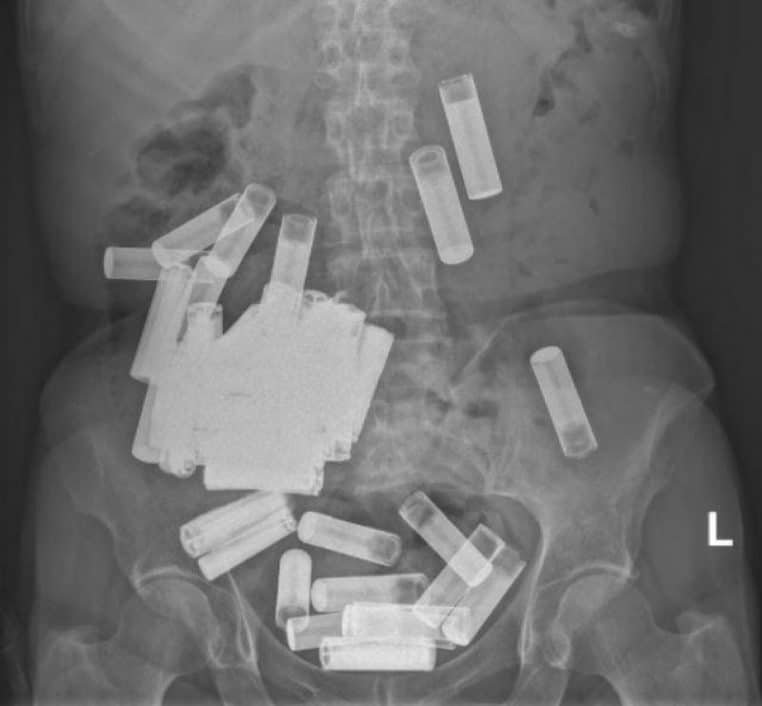

À Dublin, les médecins du St Vincent’s Hospital ont dû réaliser une opération chirurgicale particulière. Ces professionnels de santé ont retrouvé pas moins de 50 piles dans le ventre d’une femme de 66 ans.

Après avoir découvert les raisons de cette douleur suite à une radio, Irish Examiner rapporte que les analyses complémentaires n’ont montré « aucun signe d’obstruction, de perforation ou d’atteinte à l’intégrité structurelle des piles » . Les médecins ont donc décrété que les piles sortiront de son corps de manière naturelle.

5 piles ont pu s’extirper sans assistance médicale mais la situation s’est compliquée quand la patiente a senti de fortes douleurs abdominales. La femme de 66 ans a donc été opérée pour extraire les piles de son corps. Au total, 46 piles ont été retirées de son estomac et 4 de son colon. Suite au succès de l’opération, l’Irlandaise a pu sortir indemne de l’hôpital.

Même si la patiente est sortie en un seul morceau des urgences, un suivi médico-psychologique va être mis en place. L’hypothèse la plus probable reste que la sexagénaire a tenté de se faire du mal. En ingurgitant autant de piles, les chirurgiens avouent que les événements auraient pu très mal tourner. Ce geste peut entraîner « des lésions des muqueuses, des perforations et des obstructions » .